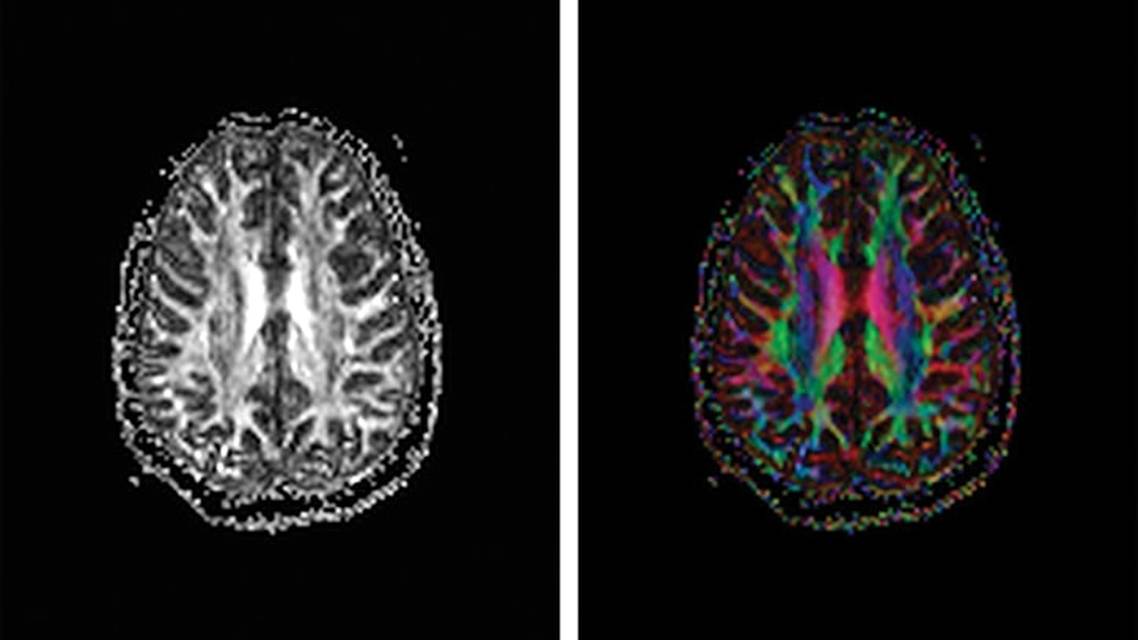

DTI acquisition encompasses a series of MR images, each representing a slice through the brain and each uniquely sensitized to diffusion along a linear direction through the 3-dimensional brain volume. DTI parameters, such as FA, are computed for each voxel in each slice. The parameter computed for each voxel can be used to create an “FA image,” where the grayscale value at each voxel represents the magnitude of FA, ranging from 0 to 1 (Figure 1A). Color FA images use a color scale to show the dominant direction of diffusion (ie, reflecting the direction parallel to the orientation of the axon bundles and tracts), and use the intensity of the color to reflect the magnitude of FA (from 0 to 1)(Figure 1B).6 However, due to the inherent spatial variation in tissue microstructure and consequent variation in FA, visual inspection of FA images can miss important abnormalities. This is a common feature of advanced neuroimaging modalities, such as perfusion imaging and functional MRI. As with these modalities, detection and characterization of abnormal FA require quantification.